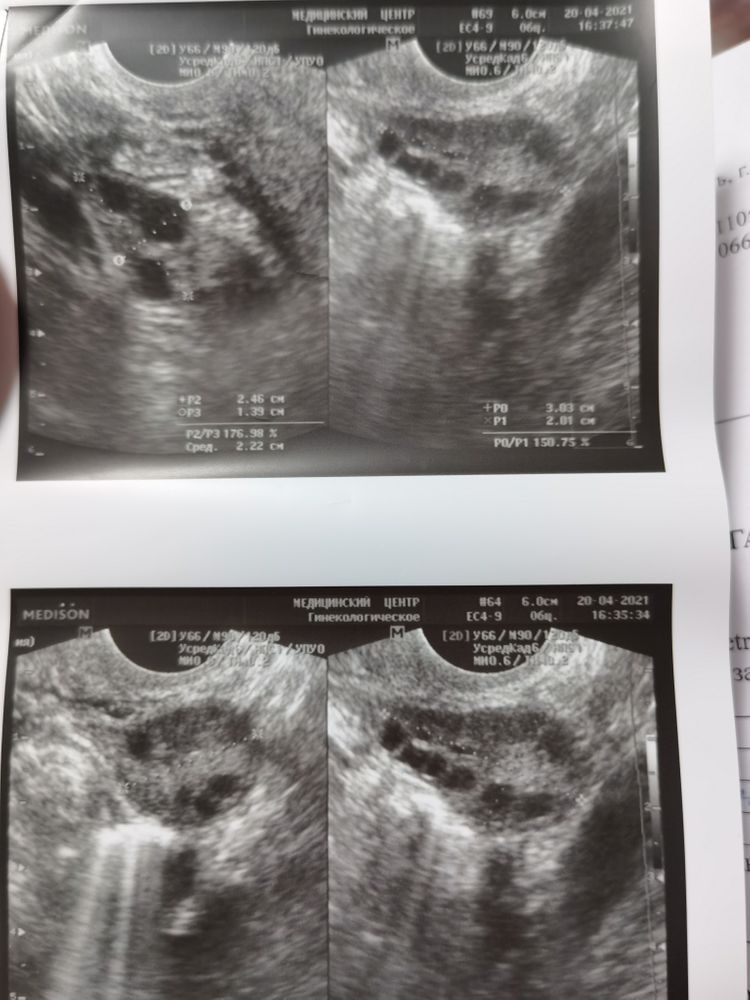

Эндометрий так и не растёт 😔цикл 37 дней. Сдала анализы на гормоны, повышен тестестерон и ЛГ. Причём что важно соотношение фсг к лг должно быть 1,5-2ум. У меня лг сильно привышает. Тестерон норма до 1.72 у меня 2.58. Остальное в норме. К врачу 11 мая, плачу и переживаю. Перелапатила интернет единственное на что думала поликистоз, но там вроде должны быть увеличены яичники. А по узи отклонений нет. Может у кого то было так? Можете поделится, пока к врачу не сходила, но зато накрутила себя.

Tanja, смотрю узи последнее, про мфя нет слова. Отмечены размеры яичников и размеры доминантных фолликулов

Ася Разманкина, по узи похоже на спкя, если видите , то много фоликулов как ожерелье. Но если у вас есть доминантные и бывает своя овуляция , то это мфя, а не спкя. Но высокий ЛГ , конечно , смущает